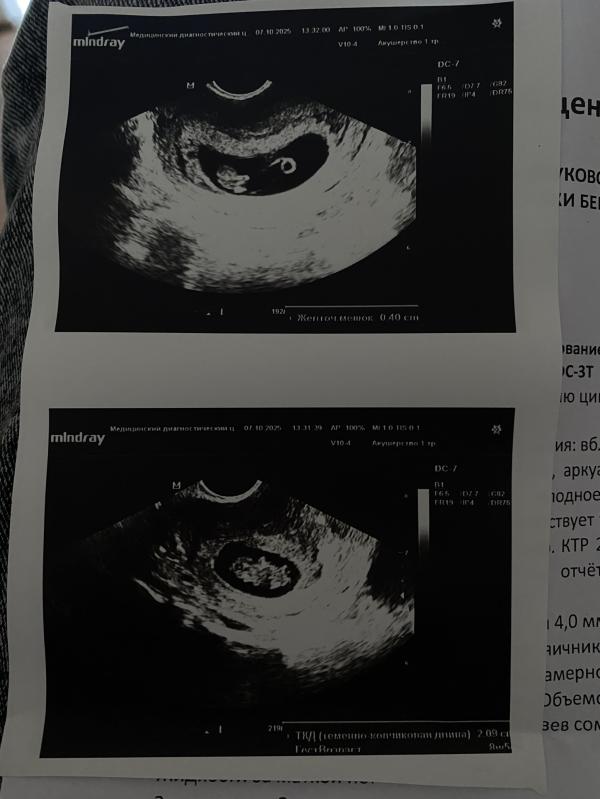

Была на узи,вот такие мы хорошенькие 🥰 сказали все отлично и больше не приходить 😹 а то я хожу каждую неделю,ну я волнуюсь ,но повода волноваться нет 🙏🏻